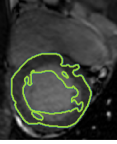

4.2 Visual assessment

We select the case that achieves the highest and lowest dice score for visual assessment. Fig. 4 shows example segmentation results where the proposed method achieved the highest agreement with the ground truth delineations. Fig. 5 shows example segmentation results where the proposed method achieved the lowest agreement with the ground truth delineations.